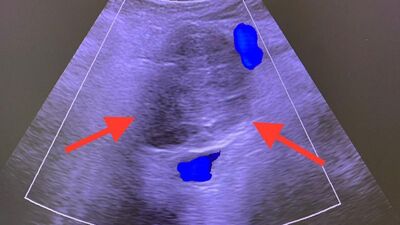

Hastanın 2010 yılında kendisine başvurduğunu belirten Radyoloji Uzmanı Doç. Dr. Mir Ali Purbager, "Renkli ultrason eşliğinde damarlar korunarak kitleye kapalı olarak ablasyon tedavisi uygulandı. Pankreas kanserinin sebebi kesin olarak bilinmemekle birlikte obezite, sigara ve alkol kullanımı, yağlı yemekler, az sebze ve meyve tüketimi, diyabet, kronik pankreatit, mide ameliyatı ve aile öyküsü gibi faktörlerin rolünün olduğu düşünülmektedir. Pankreas kanseri sinsi bir hastalık olup tanı anında hastaların yüzde 52’sinde yaygın hastalık, yüzde 26’sında bölgesel yayılım mevcut olup hastaların ancak yüzde 15-20’sinde kitle cerrahi olarak çıkarılabilir aşamadadır. Pankreas kanserinin bir yıllık genel sağ kalım oranı yüzde 26, beş yıllık ise yüzde 6’dır. Pankreas kanserinde kitle damarları sarmadıysa ve metastaz yoksa ilk tedavi seçeneği Whipple (pankreas başı, bu bölgeye yakın safra yolları ve 12 parmak bağırsağı tümörlerinde uygulanan) ameliyatıdır. Ancak hastalık sinsi ilerlediğinden genellikle tanı aşamasında ameliyat şansını yitirmektedir” ifadelerini kullandı.

Ameliyat şansını yitiren hastalarda girişimsel işlemler, kemoterapi ve radyoterapiyle yaşam süresini uzatmanın söz konusu olabildiğini kaydeden Doç. Dr. Purbager, “Pankreasın anatomik konumu nedeniyle ana damarlarla çok yakın ilişkisi mevcuttur. Ayrıca karın boşluğunun arkasında yer aldığından komşuluğundaki organlardan bu organa ve tümöre ulaşmak zordur. Girişimsel işlemler büyük bir tecrübe gerektirmektedir. Hastamıza 2009 yılında pankreas kanseri tanısı koyulmuş, başka bir merkezde ameliyata alınmıştır. Ancak ameliyat esnasında kitlenin damarlara yapıştığı anlaşılarak biyopsi alındıktan sonra kitle çıkarılmadan ameliyat sonlandırılmıştır. Hastamız 2010 yılında bize başvurduğunda kitlenin 5 santimetre çapında, çevre organlara ve damarlara yapışık olduğu görüldü. Bunun üzerine açık cerrahi yapmadan kapalı olarak renkli ultrasonla damarlar korunarak kitleye mikrodalga ablasyon (yakma) tedavisi uygulandı. Komplikasyonsuz olarak tamamlanan işlemden 1 gün sonra hasta taburcu edildi. Aralıklı olarak hasta kontrolleri yapıldı. 2 yıl sonra kitlede hafif boyutsal artış izlenince tekrar kapalı yöntemle etanol ablasyon tedavisi uygulandı. 2022 yılına kadar stabil olarak seyreden kitlede 1 cm boyut artışı saptanınca 3. kez etanol ablasyon uygulandı. Bu yöntemlerde amaç tümörün büyümesinin durdurulması, engellenmesidir. Bu 12 yıl süre zarfında hasta aktif olarak yaşamını sürdürüyor, mesleği olan çiftçiliği, arıcılığı yapıyor. Burada vurgulanması gereken bir nokta pankreas kanseri tanısı alan hastalarda cerrahi şansı varsa ilk tedavi yönteminin cerrahi olduğunun bilinmesidir. Ablasyon tedavisi sadece cerrahi şansı olmayan hastalara uygulanmaktadır ki hastamız Celal Açıkgöz de böyle bir hastaydı. Radyolojik girişimsel yöntem uyguladığımız hastamız 13 yıldır pankreas kanseriyle normal hayatını yaşıyor. Şu an tümör stabil, 6 cm. takip edilecek, gerekirse tekrar ablasyon uygulanabilir” diye konuştu.